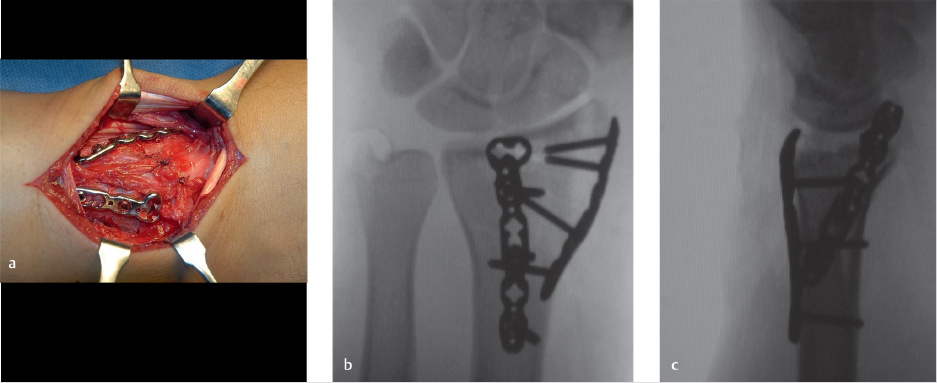

Three-dimensional CT reconstructions show the volar rim of the radius to be intact with the dorsal small shearing fracture fragments (► Fig. 44.3). Also seen in all the preoperative images is the radial styloid fracture. Notice the horizontal fracture line involving the entire scaphoid fossa and continuing to the dorsal cortical rim. Operative fixation was recommended. A standard dorsal approach to the wrist was used, with a longitudinal incision over distal radius and radiocarpal joint in line with the 3rd metacarpal. The extensor pollicis longus tendon was mobilized from the 3rd dorsal compartment and the tendons of the second and fourth dorsal compartment were retraced to gain exposure (► Fig. 44.4). The dorsal small rim and the radial styloid fractures are clearly visualized. Usually the capsule is torn (► Fig. 44.4), but if it is intact, a dorsal arthrotomy is made parallel to the dorsal rim to inspect the articular surface and look for any associated carpal injury. At this point, carpus is reduced and fixation is started with the less comminuted fracture fragment. In this case, a 0.062 smooth K-wire was used for provisional fixation of the radial styloid fracture, and articular reduction was also confirmed using intraoperative fluoroscopy (► Fig. 44.4). If dorsal rim fragments are adequately large, provisional fixation can be obtained with K-wires. If they are too small, they can be held with suture anchors or transosseous sutures. Low-profile dorsal-distal radius plates were then used for fragment-specific fixation (► Fig. 44.5). Radial column plate and 2.4 mm dorsal plate were used. Capsule was repaired using resorbable suture (► Fig. 44.5). Follow-up at 8 months showed excellent function with some loss of wrist extension and flexion (► Fig. 44.6). Many plates are available for these fractures. The most recently designed plates have variable angle locking screws. The dorsal plate should be applied as distally as possible. These plates might need some contouring to fit the distal radius metaphysis and the radial styloid.